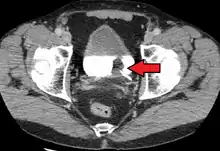

If invasive or high grade (includes carcinoma in situ) cancer is detected on TURBT, an MRI and/or CT scan of the abdomen and pelvis or urogram and CT chest should be conducted for disease staging and to look for cancer spread (metastasis).[56] Increase in alkaline phosphatase levels without evidence of liver disease should be evaluated for bone metastasis by a bone scan.[57] Although 18F-fluorodeoxyglucose (FDG)-positron emission tomography (PET)/CT has been explored as a viable method for staging, there is no consensus to support its role in routine clinical evaluations.[54]